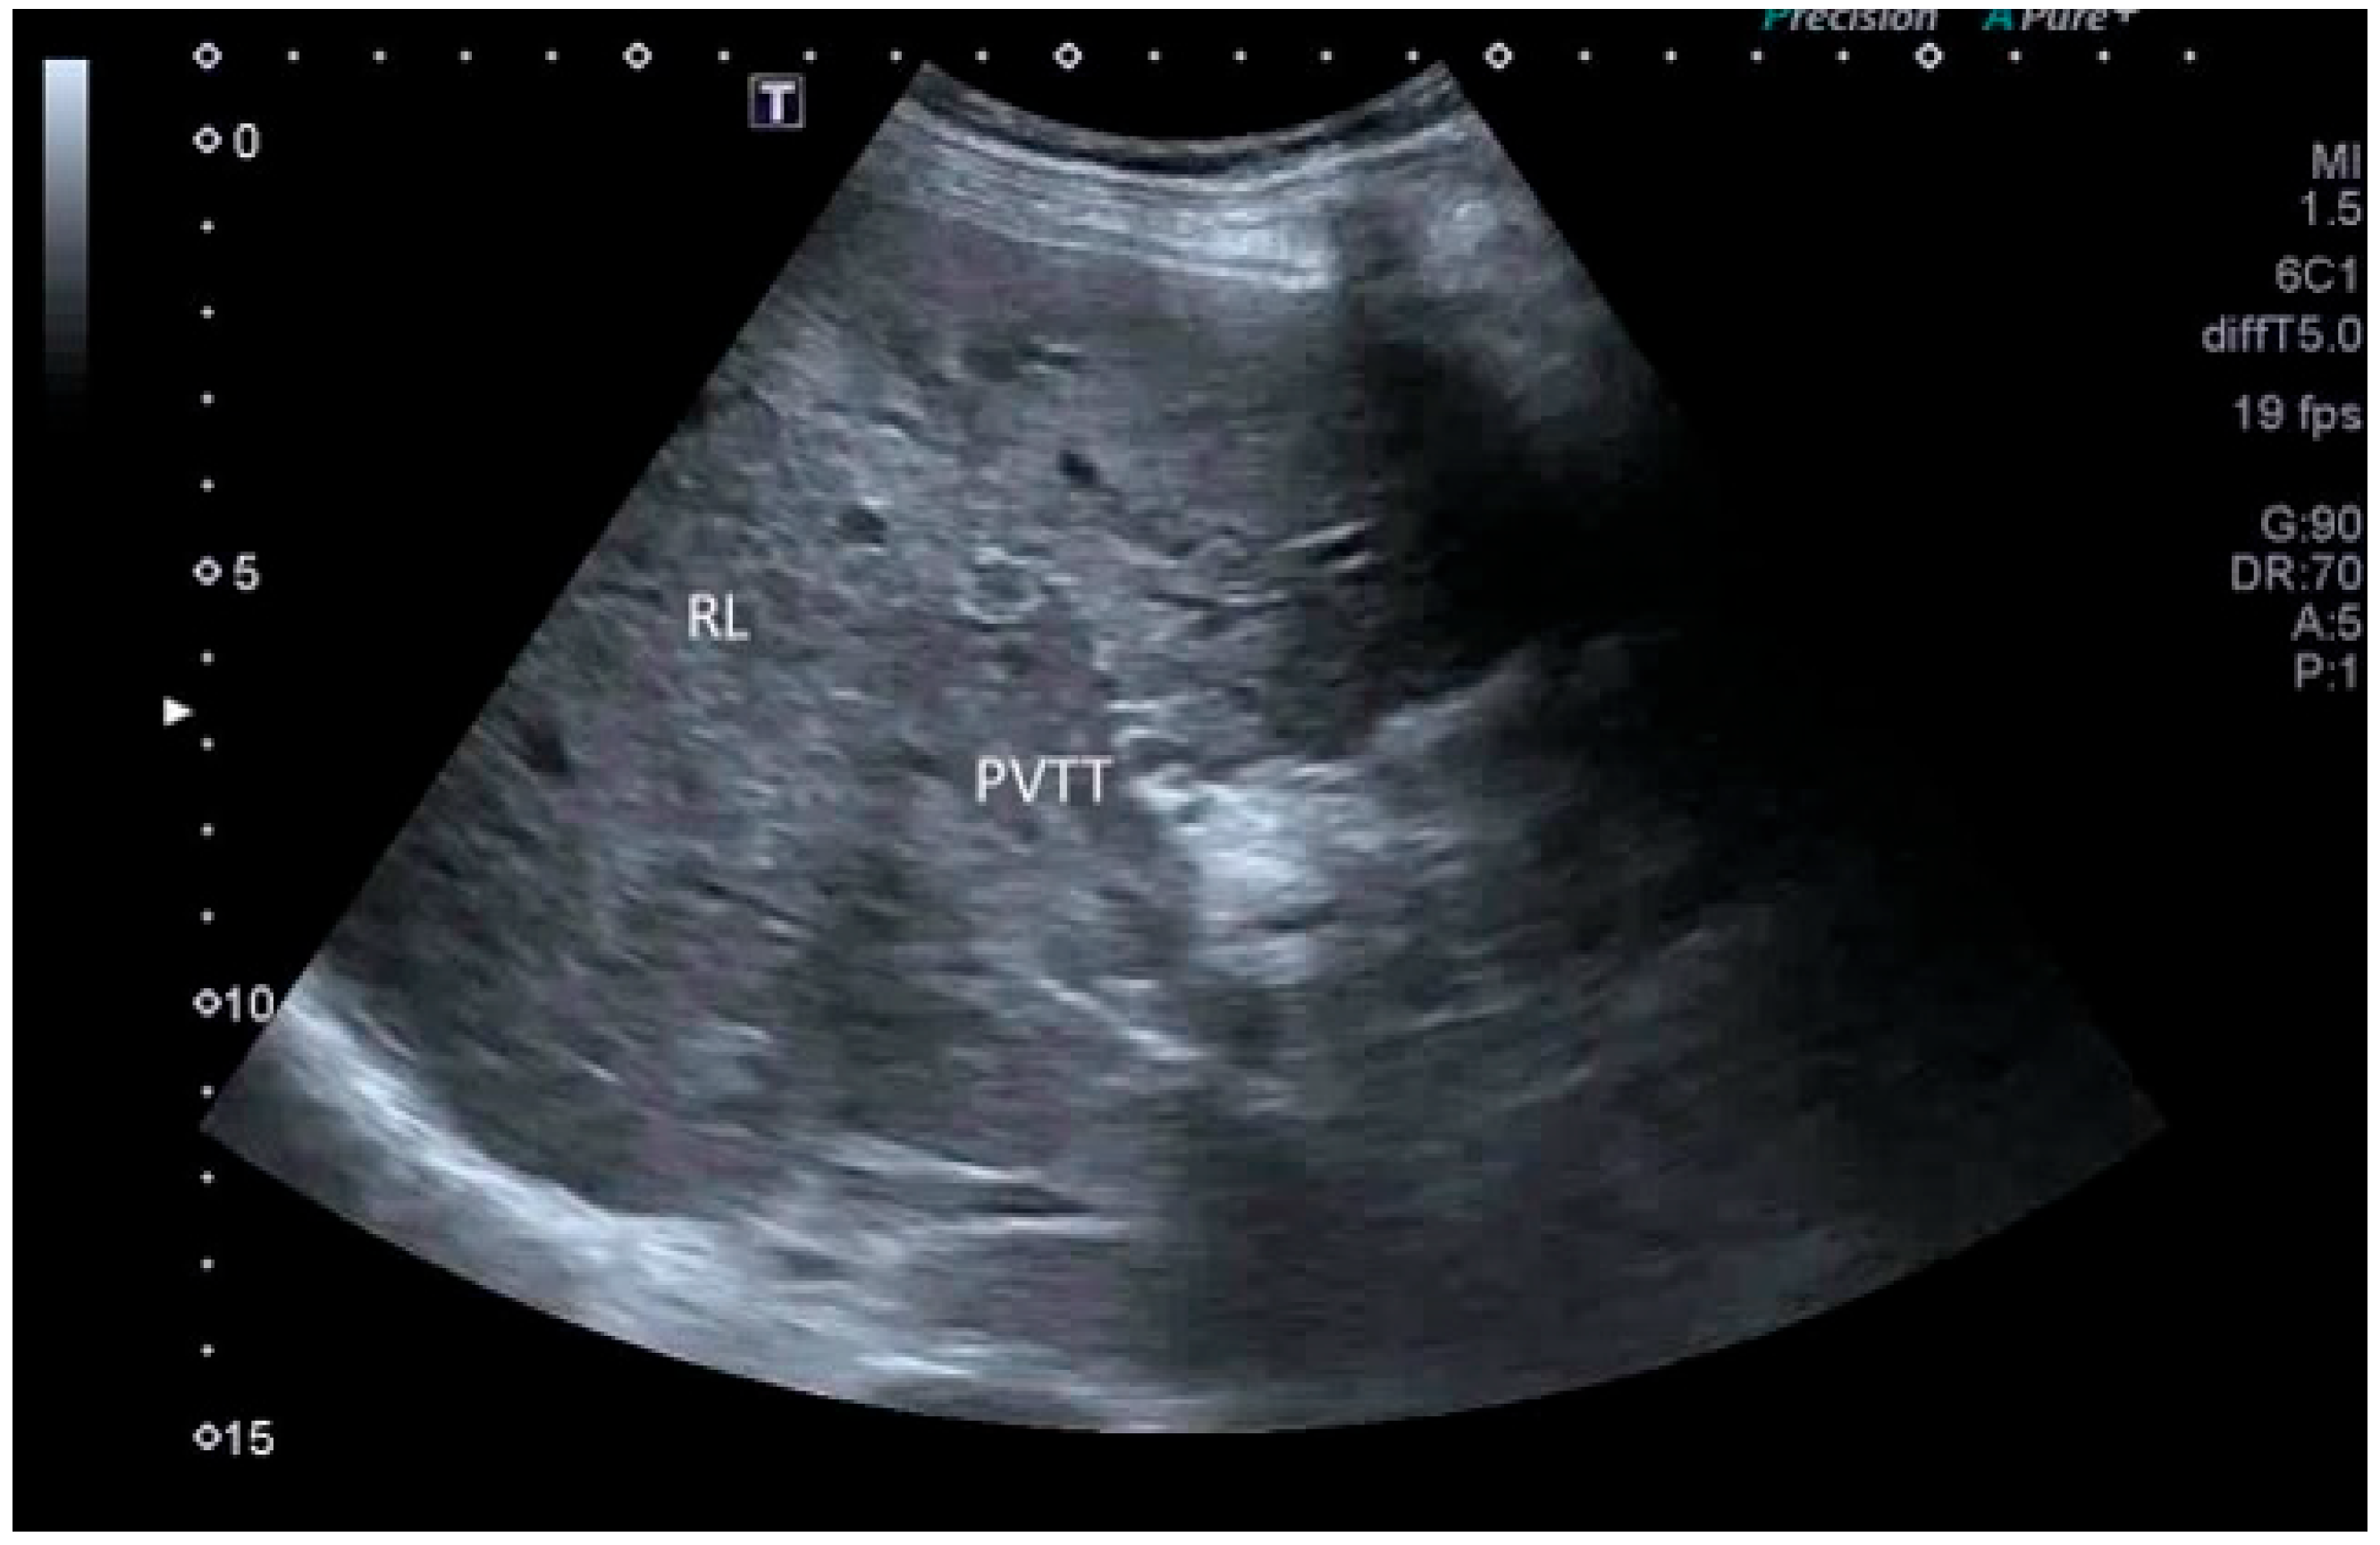

- Cerrito, L.; Ainora, M.E.; Di Francesco, S.; Galasso, L.; Gasbarrini, A.; Zocco, M.A. The Role of Contrast-Enhanced Ultrasound (CEUS) in the Detection of Neoplastic Portal Vein Thrombosis in Patients with Hepatocellular Carcinoma. Tomography 2023, 9, 1976–1986. [Google Scholar] [CrossRef] [PubMed]

| CEUS LR-TIV (tumor in vein) |

|